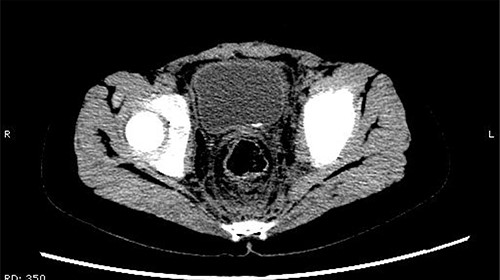

On 25 February, the patient complained of left back pain, nausea and vomiting. A further CT scan showed some irregular high-density shadows persisted in the left renal pelvis (Fig. 3) and an irregular high-density shadow was present in the left upper ureter (Fig. 4); furthermore, hydronephrosis was apparent in the left renal pelvis. There were no abnormalities in the bladder.

An irregular high-density shadow was present in the left upper ureter.